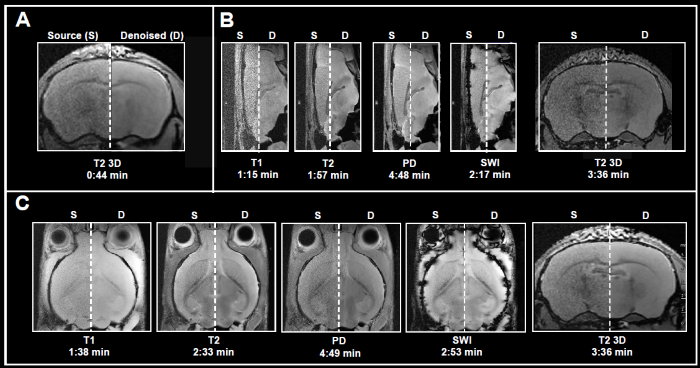

Fig. 4 displays examples of ex vivo brain scans of different contrasts and orientations gathered in less than 5 minutes. The data was obtained from 3, 7, and 9.4 Tesla tools. To achieve the desired short acquisition time, standard protocols prepared for each system were improved by removing averaging, as seen in Fig. 4A-C.

This resulted in 7-15 times faster acquisition times compared to the original protocols. Yet, given the chosen resolution, no averaging resulted in noisy images. Reconstructing the obtained data with the denoising algorithm successfully removed noise from images and delivered high-quality images.

Figure 4. Examples of fast brain scans. Ex vivo data of a fixed mouse head acquired with different image contrasts, geometries and orientations. Data were acquired at A) 3 Tesla, B) 7 Tesla, and C) 9.4 Tesla. Images were reconstructed with no denoising (Source) and with a network Strong and applying 50% pre-denoising and a denoising level of 70% (Denoised). Image Credit: Bruker BioSpin Group